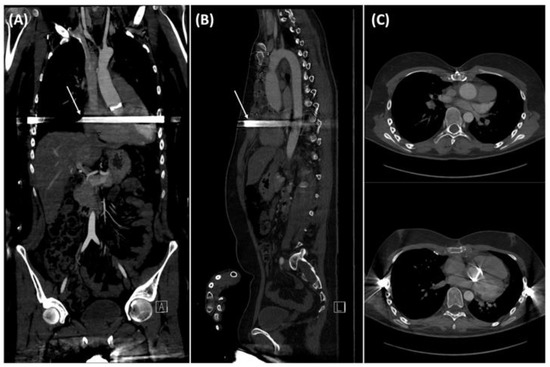

2. Case Description